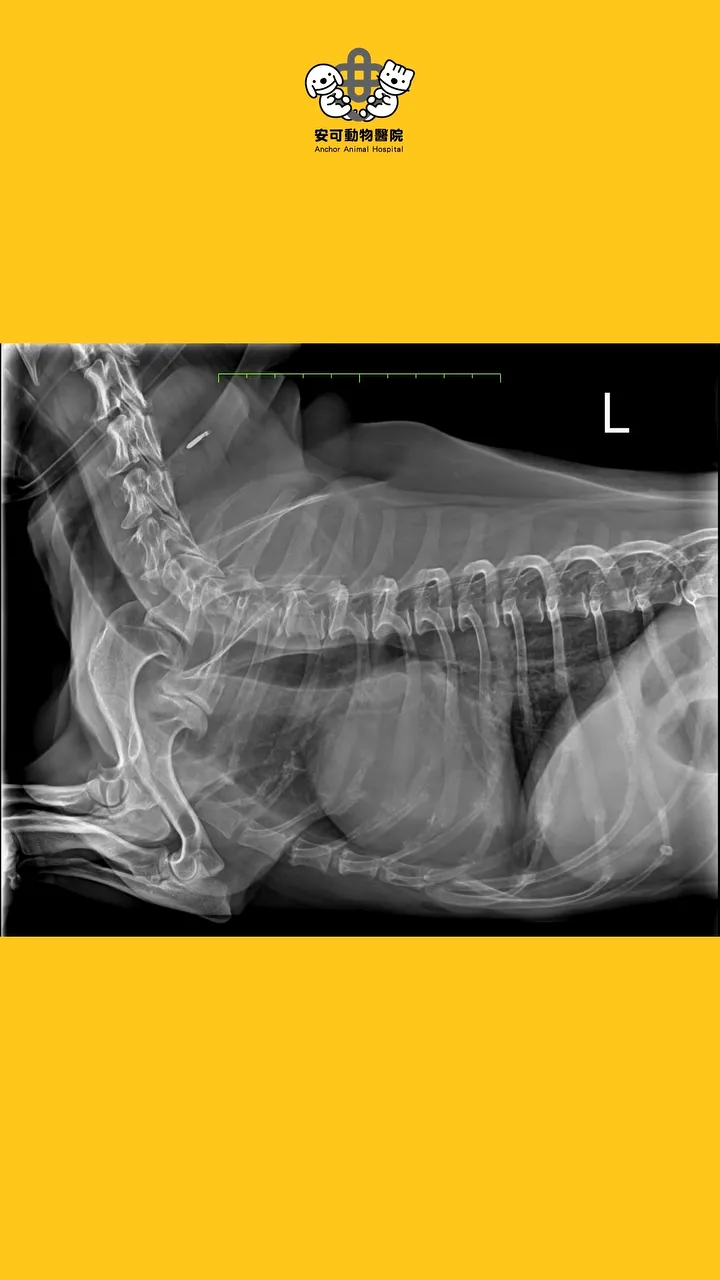

🩻第二步: X光檢查,心臟輪廓變大(VHS=11.0);肺葉呈現肺泡型病徵(alveolar pattern)。

🩻第二步: X光檢查,心臟輪廓變大(VHS=11.0);肺葉呈現肺泡型病徵(alveolar pattern)。